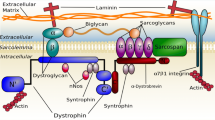

All muscular dystrophies (MD) are rare orphan diseases, characterized by progressive muscle weakness resulting in functional disability. While the causes for muscle weakness vary between different MDs, they share common histological features, including fibrosis, muscle edema, and fat replacement of muscle tissue. More than 70 distinct variants have been identified, some becoming apparent in early childhood with rapid progression while others are not detected until adulthood with a much slower timescale of progression. Among the muscular dystrophies, Duchenne muscular dystrophy (DMD) is the most common form affecting 1 in 3500–6000 male births [1, 2], tending to show first symptoms at 3–5 years of age and rapid progression leading to loss of ambulation between 10 and 15 years. Deterioration of respiratory function and cardiomyopathy occur in DMD and in many other MDs.

Therefore, it is essential to have outcome measures that are less dependent on patient cooperation and motivation while being sufficiently sensitive to measure treatment effects even in small and highly heterogeneous patient populations. Quantitative muscle MRI (qMRI) can provide such an outcome measure, as it is non-invasive and can generate a wide range of imaging contrasts over large volumes of muscle. As such, it can visualize and quantify the major hallmarks of muscle degeneration in MDs: muscle hypertrophy and atrophy, muscle edema and inflammation, and the replacement of muscle tissue by fat tissue. Histologically, the content of the muscle fibres is progressively replaced by lipid, resulting in a fatty tissue. On MRI, the overall outline, shape, structure, and appearance of the muscle groups are often preserved despite the extensive fatty tissue content. In contrast to functional scores obtained by physical assessment, qMRI is less biased by patients or observers. Excellent reproducibility of qMRI has been demonstrated in healthy volunteers as well as in patients [5, 6]. In particular, qMRI of fat replacement has the potential to be very valuable as an outcome measure in clinical trials as it has been shown to be more sensitive than clinical evaluation in detecting disease progression [7,8,9,10,11,12] and effect sizes of fat replacement measured by qMRI are much greater than those of commonly used clinical scores [10, 13]. Thus, when using qMRI of fat replacement as an end-point to demonstrate the effectiveness of a putative novel treatment, the number of patients required is markedly reduced [9, 10]. Although invasive muscle biopsy is sometimes undertaken (often to determine membrane protein expression) and fat content could be estimated from it, it is an unreliable method of measuring fat content due to the small sample volume, the heterogeneous nature of the fat replacement across muscle groups, and the limitations on repeating biopsy in longitudinal studies.